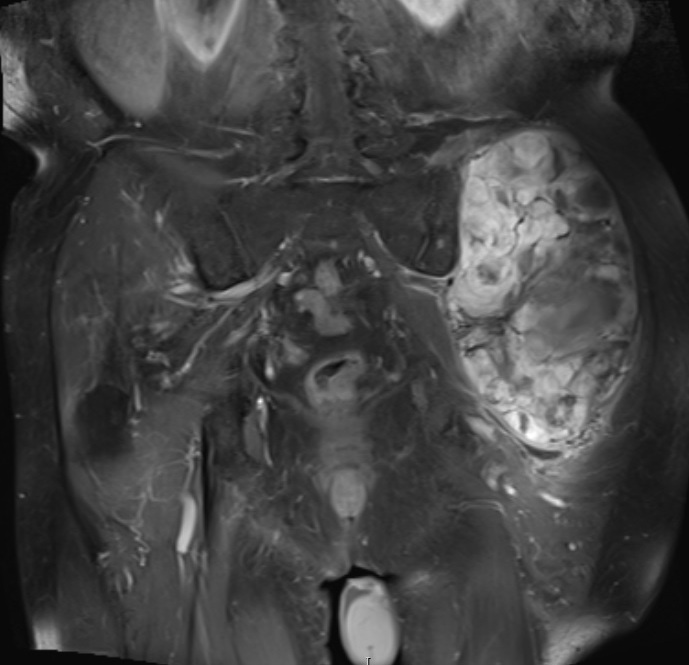

Axial (Fig. 4) and Coronal (Fig. 5) contrasted T1-weighted MR images show a large heterogeneous mass with central and peripheral enhancement. Central low signal intensity image is compatible with necrosis and hemorrhage.